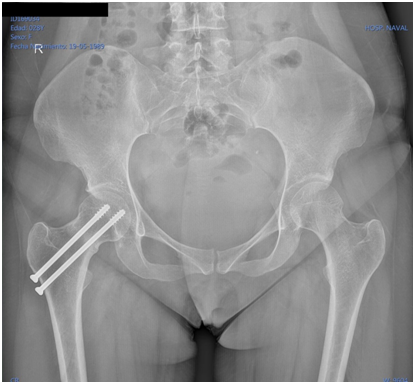

Female patient of 25years-old, active military, size 165cm, weight 52kg, BMI 19.1, with antecedent of military training for about 5 to 6hours a day, 6days a week, for 2months prior to the onset of symptomatology. She refers with discrete right inguinal pain, which increased with physical effort, radiating towards the proximal third of the thigh and right buttock. It is evaluated by a general physician and diagnosed as a muscle contraction, without abnormalities in the x-ray exam (Figure 1) indicating treatment with analgesics and non-steroidal anti-inflammatory drugs, without suspension of physical activities. She comes back to the emergency department of the Naval General Hospital of High Specialty one week later, referring an acute increase in the symptoms and limitation of movement due to pain, an antero posterior pelvic radiograph is performed, without data of apparent bone lesion (Figure 2).

Figure 1 24/08/2015 anteroposterior pelvic radiograph, taken on the day of admission, with no data of apparent bone lesion.